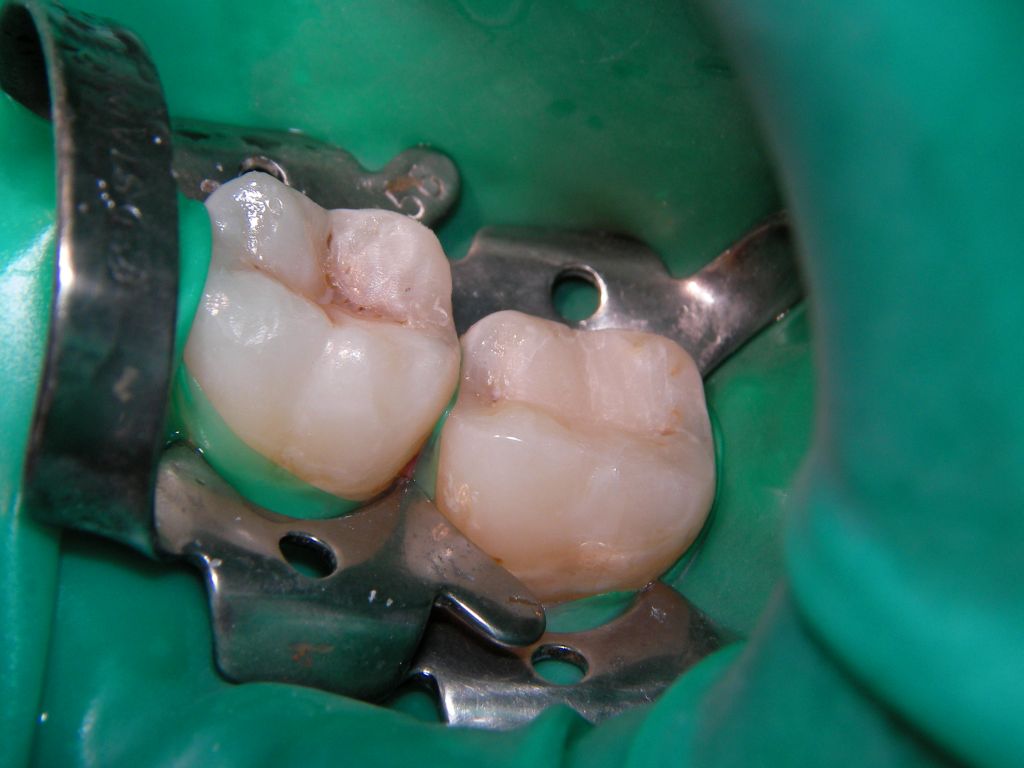

![]() | Am Ende waren es sogar 3, nicht nur 2 Füllungen (wer sieht die 3.?). Das grüne Latexgummi ist Kofferdam (=Spanngummi), der manchmal die Arbeit erleichtert, weil er den Speichel fernhält. Zuzahlung für die Kassenpatientin 2 * 30 . Mit Speichelfilm sind solche Füllungen im Alltag nicht mehr zu erkennen. |

![]() | |||||||||||||||||||||||||||||||||||||||||||||||||||||||||||||||||||||||